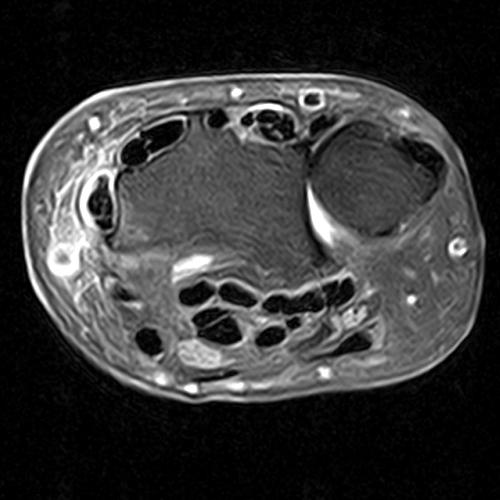

Clinical History: A 68-year-old female presents with radial-sided pain and swelling. Axial T1-weighted (1A), axial fat-suppressed proton density-weighted (1B), and coronal fat-suppressed proton density-weighted (1C) images are provided. What are the findings? What is your diagnosis?

Figure 2: The axial T1-weighted (2A), axial fat-suppressed proton density-weighted (2B), and coronal fat-suppressed proton density-weighted (2C) images demonstrate a thickened extensor retinaculum, surrounding soft tissue edema, and fluid signal in the first extensor compartment of the wrist (arrowheads). Marrow edema is noted within the subjacent radius (asterisks). A single extensor pollicis brevis and two abductor pollicis longus tendon slips are present with heterogeneous intrinsic signal.